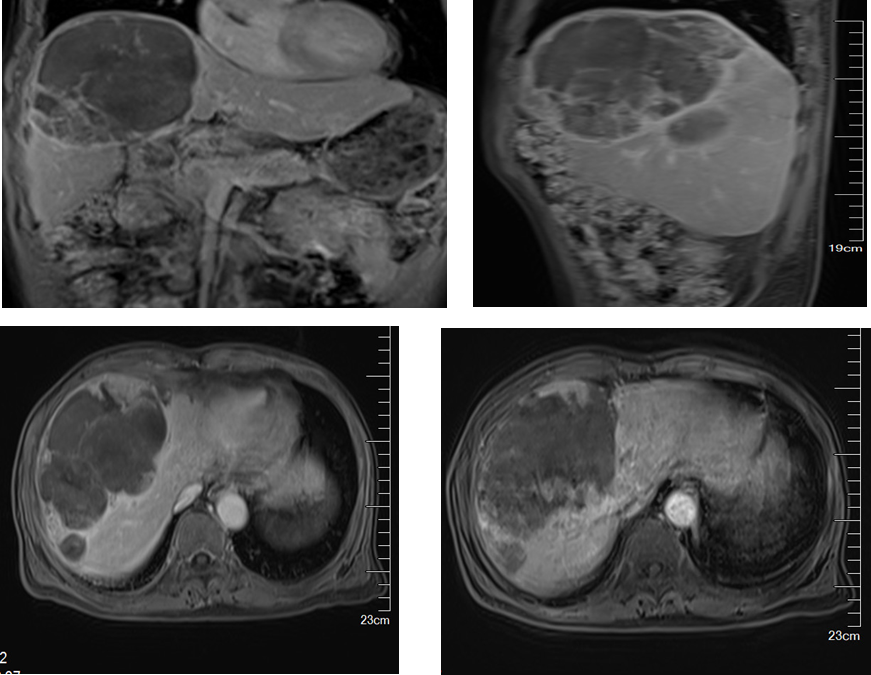

2020年11月19日(第2次介入术后1月余)

肝实质内可见多发软组织肿块影,呈等/稍长/稍短T1、稍长/短T2异常信号,增强扫描动脉期病灶内见斑片状明显强化灶,门脉期及平衡期持续强化,延迟期见假包膜强化,病灶部分融合,病灶大者约11.1cm×13.2cm×9.9cm。肝门及右侧心膈角区可见多发增大淋巴结,大者短径约8mm。

影像诊断:

与前片(SMR200914033)比较:部分肿块较前缩小,病灶内见多发坏死灶,建议随诊复查;肝包膜下积血、积液减少;肝门部及右侧心膈角区多发增大淋巴结,部分稍缩小;肝硬化、腹水减少;肝段下腔静脉狭窄。APT:2313 ug/L

2020年12月30日(第3次介入术后1月余)

影像表现:肝脏形态不规则,肝裂增宽,肝实质内可见多发软组织肿块影,呈等/稍长/稍短T1、稍长/短T2异常信号,增强扫描动脉期病灶内见小片状明显强化灶,门脉期及平衡期持续强化,延迟期见假包膜强化,病灶部分融合,病灶大者约9.7cm×12.5cm×9.2cm。

影像诊断:与前片(SMR201118073)比较:部分肿块较前缩小,病灶内异常强化灶范围缩小,病灶内多发坏死灶,建议随诊复查;肝门部及右侧心膈角区多发增大淋巴结,较前无明显变化。